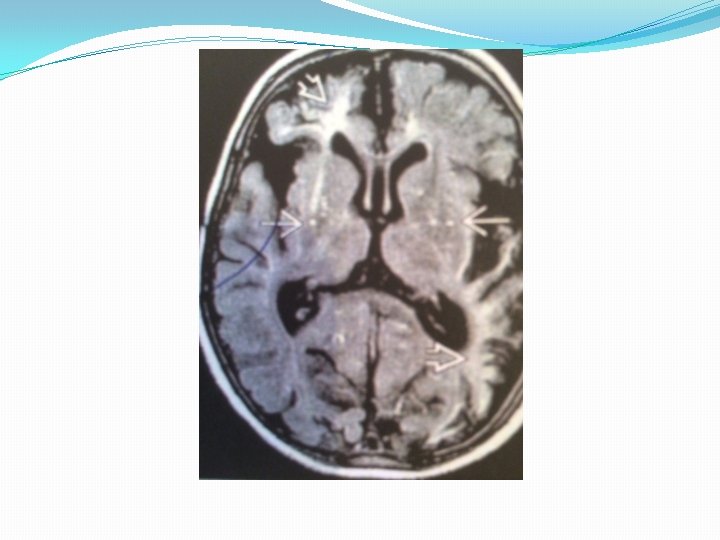

Imaging �Best diagnostic clue: multiple punctate dots (CECT) and flow voids(MR) in basal ganglia �Location : circle of willis ; anterior>>> posterior circulation �Morphology: “puff of smoke” cloud like lenticulostriate and thalamosrtiate collaterals on angiography

Imaging MRI finding �T 1 WI: Multiple dot like flow voids in BG �T 2 WI: Increased signal of small vessel and cortical and white matter infarct �FLAIR: Bright sulci=leptomeningeal “ivy” sign (slow flowing engorged pial vessels , thickened arachnoid membrane �T 1 WI C+: Enhancing dots in BG correlates with lenticulostriate and thalamostriate collaterals